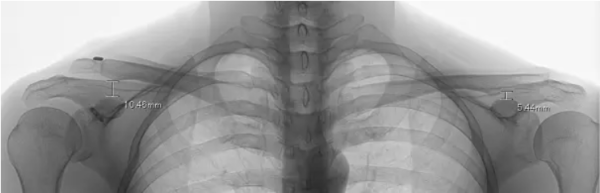

This patient underwent coracoclavicular ligament reconstruction and has been followed for 10 years. Postoperatively, displacement of the right acromioclavicular joint has been observed; however, the degree of displacement is less than it was before surgery.

This is an X-ray taken 10 years after the surgery.